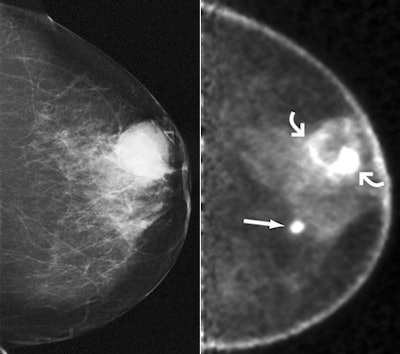

| Images obtained in 68-year-old woman who previously underwent right mastectomy for cancer and was noted to have lump in left breast. (above, left) Lump was shown to correspond to 2.8-cm indistinctly marginated mass (triangular marker) on craniocaudal mammogram. Ultrasound-guided core-needle biopsy revealed grade III invasive ductal carcinoma (IDC). (above, right) Craniocaudal and (below, left) mediolateral oblique PEM images (5.6-mm section thickness) obtained beginning 70 minutes after intravenous injection of 10.4 mCi (384.8 MBq) of FDG show intense rim uptake in known cancer (curved arrows). Approximately 5 cm medial and inferior to this region, intense FDG uptake was noted in second, 1-cm mass (straight arrow). |